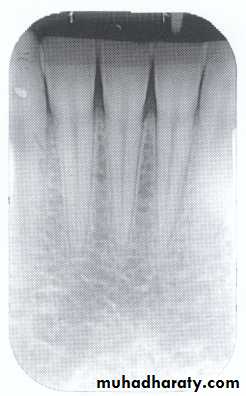

Between the anterior teeth the alveolar crest normally is pointed and well corticated.

Mild bone loss: crestal changes (The anterior regions show blunting of the alveolar crests and slight loss of alveolar bone height.Posteriorly show loss of the normally sharp angle between the lamina dura and alveolar crest).

Mild bone loss

Classification of Periodontal Disease

Type-I: there is no bone loss associated with this type but only gingivitis, & no radiographic changes are seen.

Type-II: there is mild periodontitis, & mild crestal changes.